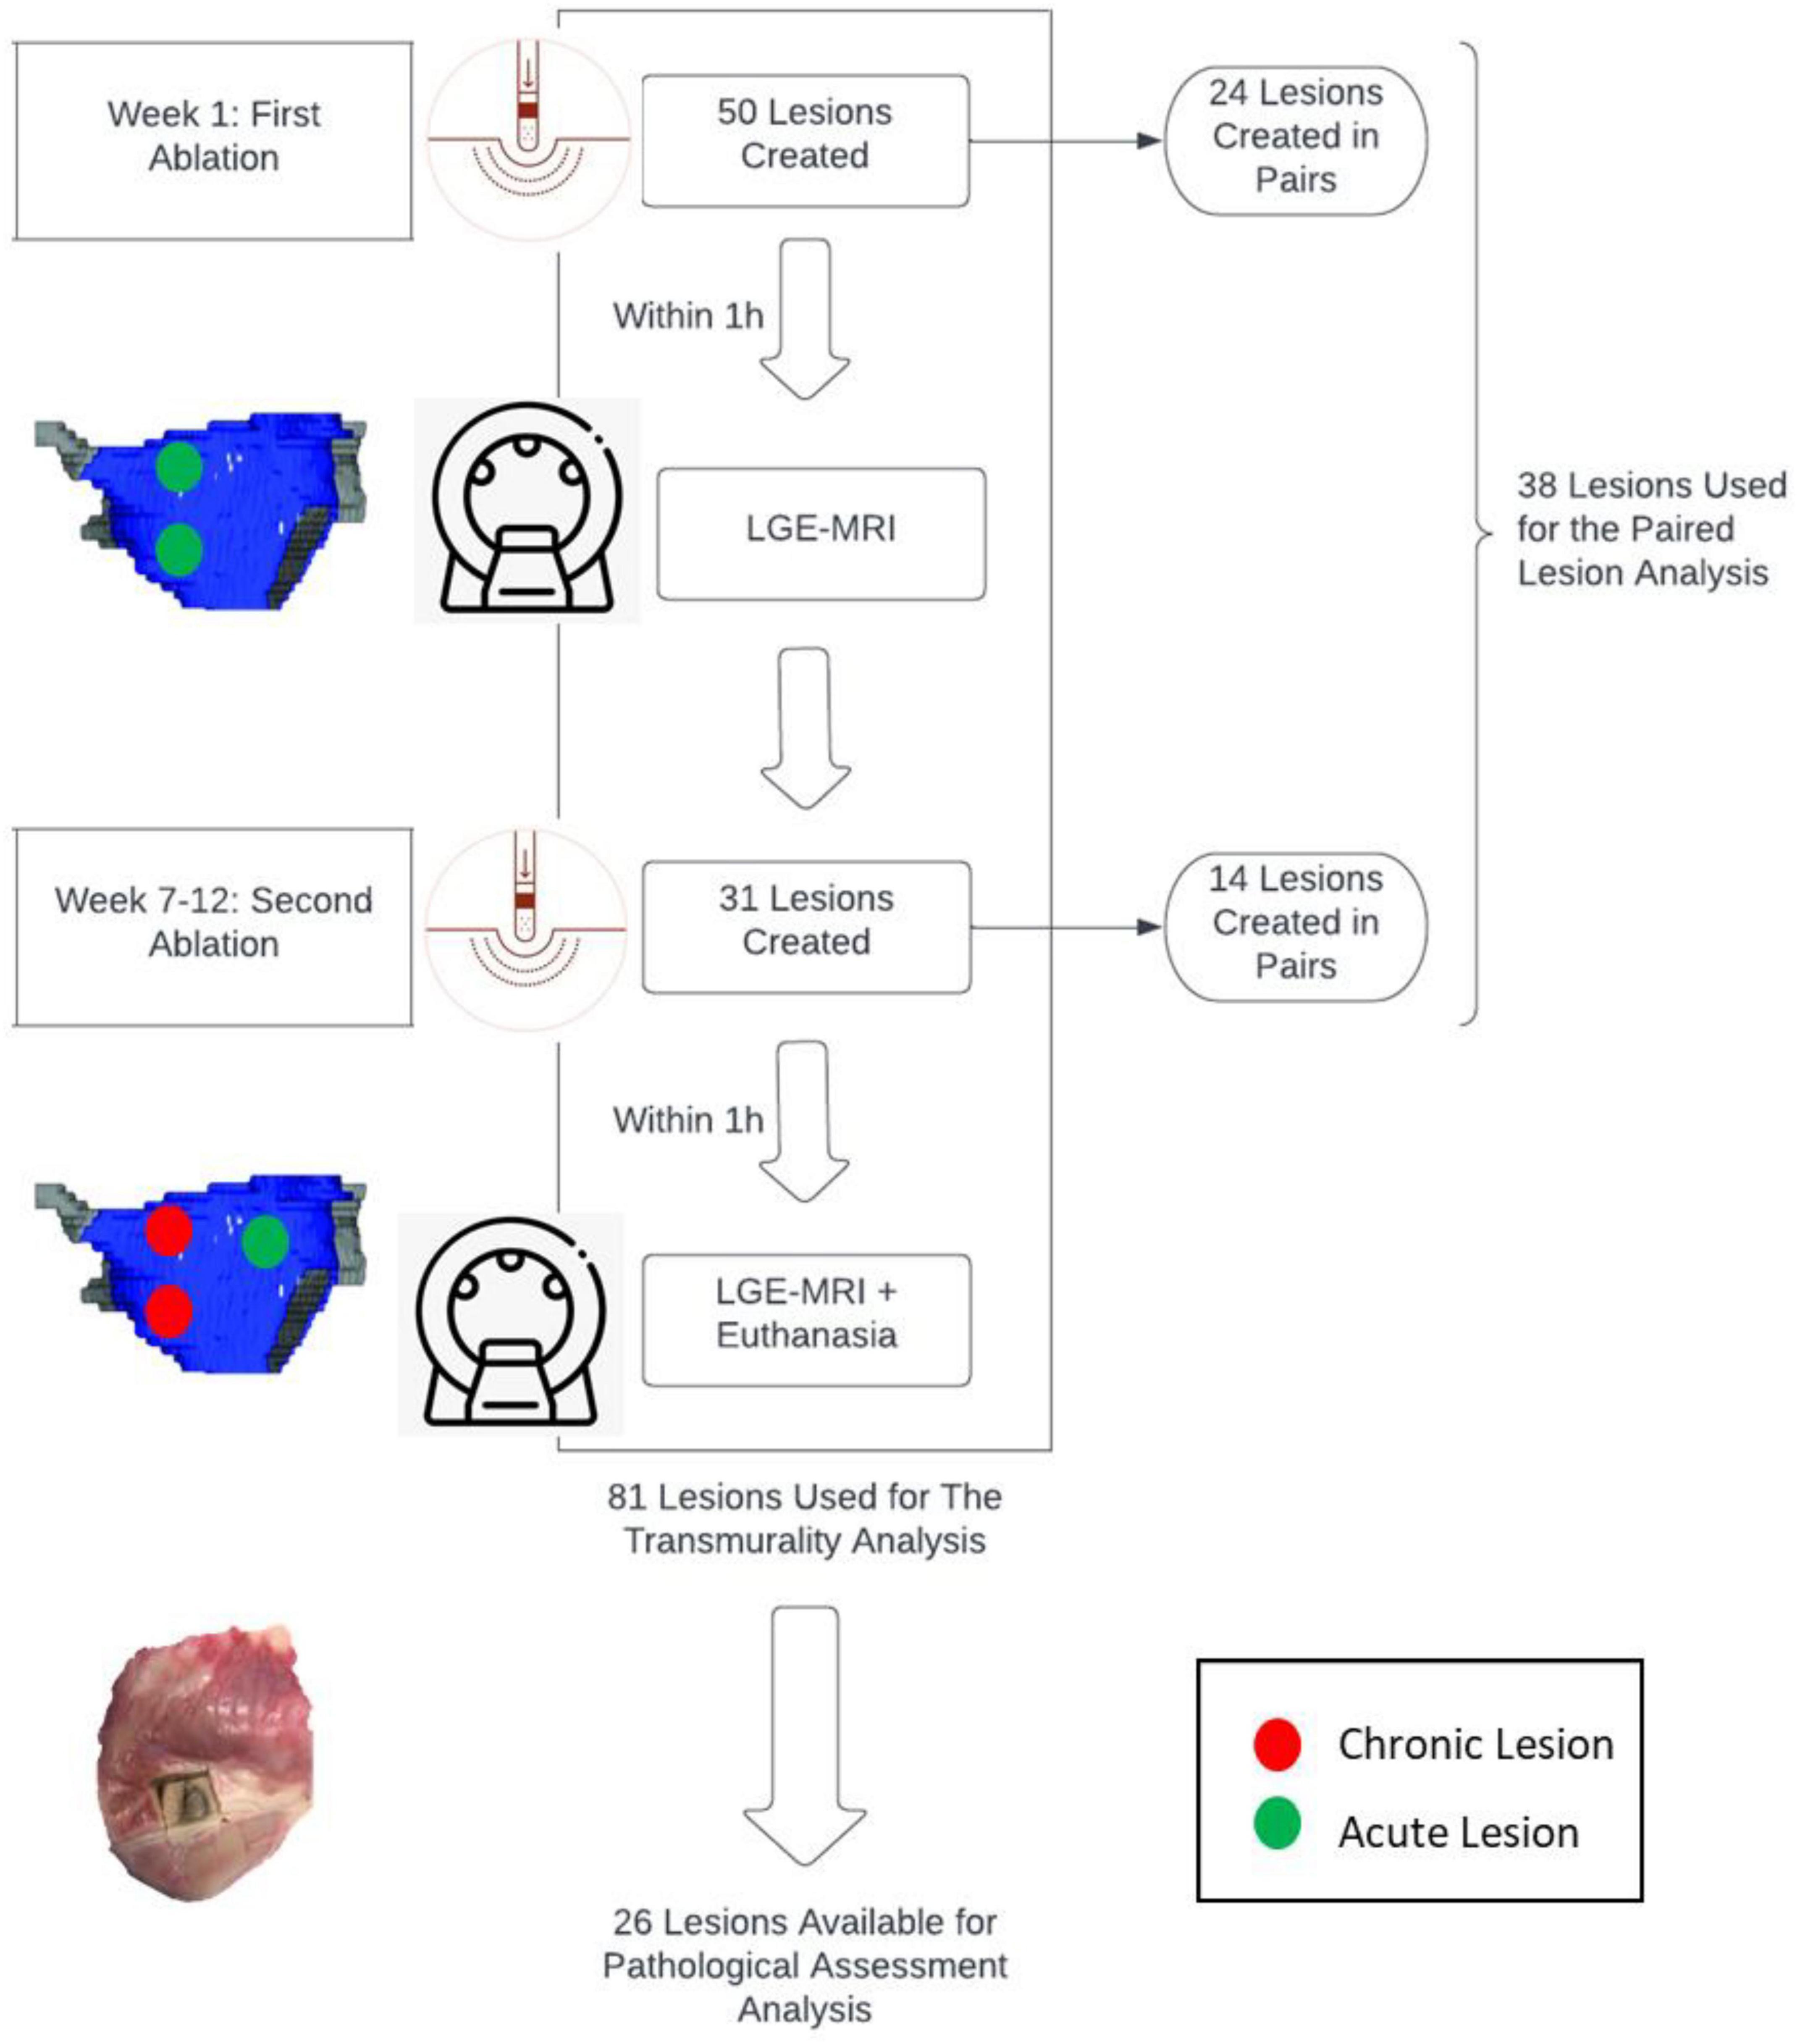

Materials and Methods: Ablation procedures were performed on 7 canines followed by late gadolinium enhancement MRI (LGE-MRI). Transmurality of lesions was assessed by 2 independent operators. Ablation parameters such as duration (s), power (W), temperature (C), contact force (CF) (g), were collected for each ablation point. After 7-12 weeks, LGE-MRI was performed, followed by euthanasia, and heart excision. Some lesions were created in pair. Lesion pairs were spaced 7-21 mm apart as measured by Electroanatomic mapping (EAM), with different operating parameters (power 35 or 50W, duration of energy delivery 10, 20 or 30s and contact force of 10g or above). We performed a logistic regression analysis to determine predictors of transmural lesion formation.

Initially, animals were scanned via MRI to establish the baseline anatomy of the cardiac chambers. Approximately one week later, the first of two ablation procedures were performed followed immediately by MRI of these acute lesions. Between 7 and 12 weeks following the first ablation, a terminal study was performed whereby an additional ablation procedure was carried out which was immediately followed by MRI, euthanasia, and heart excision.

We created 81 radiofrequency ablation lesions in the left (LV) and right (RV) ventricles of 7 canines. Out of those 81 lesions, 33 ablation lesions were in the LV and 48 in the RV.

Out of the 81 lesions, we performed thirty-eight paired ventricular lesions. A total of twenty-four unconnected (twelve pairs) lesions were created and equally distributed in the left ventricle (LV), right ventricle (RV) and septum. A total of fourteen connected lesions were created (seven pairs), eight of which are in the LV. There was no significant difference in force and temperature used in both groups (p > 0.05). However, there was a significant difference in EAM distance between connected and unconnected lesions (p < 0.05).

All characteristics of the paired lesions are summarized in Table 1. A flow chart summarizing the study is seen in Figure 1.